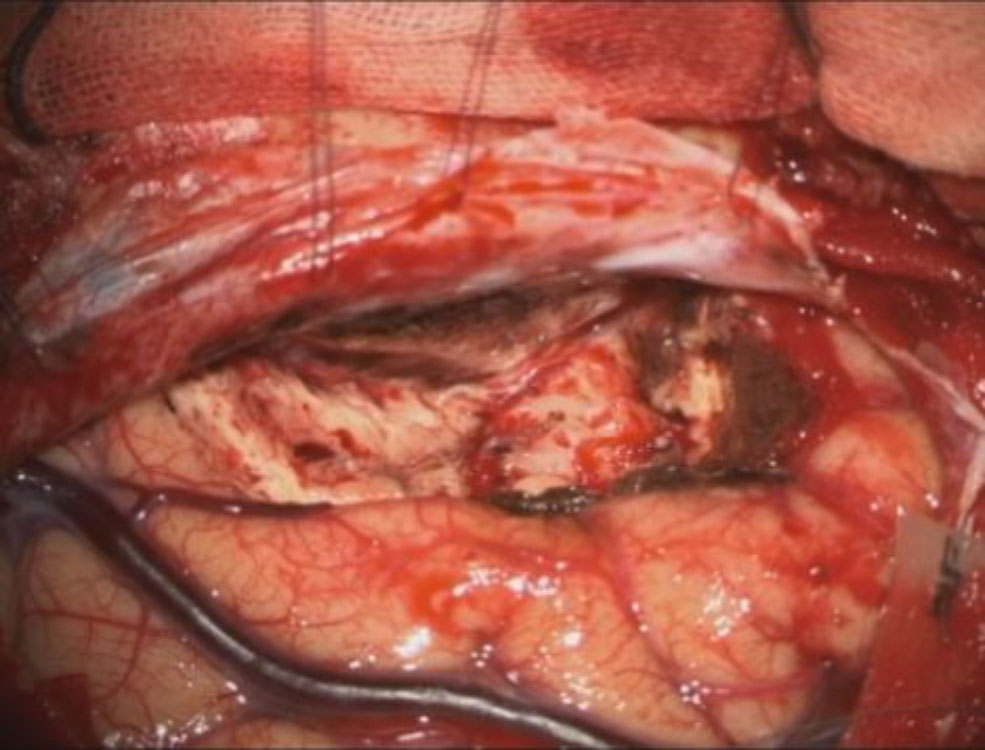

術中写真

摘出 前

摘出 中

摘出 後